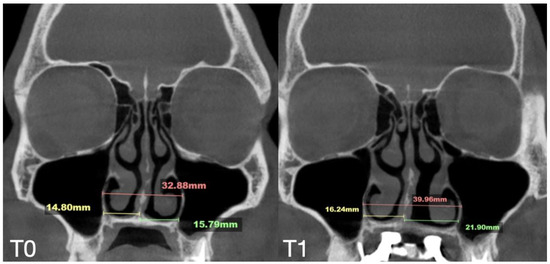

| Nasal Base Width, mm | Maxillary Base Width, mm | Lateral Nasal Width, mm | Inter-Pterygoid Distance, mm | Midpalatal Suture Separation, mm | |||||||||

|---|---|---|---|---|---|---|---|---|---|---|---|---|---|

| T0 | T1 | T2 | T0 | T1 | T2 | T0 | T1 | T2 | T0 | T1 | T2 | T1 | |

| Case A | 30.84 | 38.15 | 38.37 | 59.22 | 66.37 | 67.11 | 32.8 | 39.33 | 39.48 | 28.01 | 32.88 | 33.38 | 10.5 |

| Case B | 30.61 | 34.41 | 34.97 | 59.73 | 63.47 | 60.56 | 31.79 | 34.6 | 35.35 | 29.18 | 31.38 | 34.59 | 5.7 |

| Case C | 28.40 | 38.32 | 36.72 | 53.63 | 62.43 | 59.80 | 31.29 | 38.45 | 38.51 | 29.15 | 35.8 | 35.36 | 8.47 |

| Case D | 26.25 | 33.27 | 31.54 | 55.9 | 61.84 | 60.37 | 33.98 | 35.94 | 38.09 | 29.77 | 29.24 | 29.02 | 6.2 |